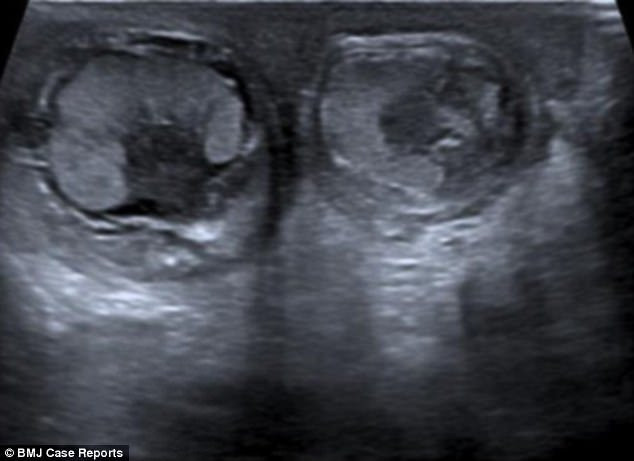

Đến ngày tuổi thứ ba, cậu bé được siêu âm tinh hoàn và phát hiện bị xoắn. Các bác sĩ khoa tiết niệu của bệnh viện tin rằng cậu bé đã bị xoắn tinh hoàn ngay từ khi còn trong bụng mẹ.

Theo các bác sĩ, đây là trường hợp rất hiếm và vẫn chưa thể hiểu nguyên nhân vì sao cậu bé lại bị xoắn cả hai tinh hoàn.

Các thống kê cho thấy, tỷ lệ trẻ bị xoắn tinh hoàn chỉ khoảng 6/100.000 bé. Phần lớn chỉ là xoắn một bên tinh hoàn. Trường hợp bị xoắn cùng lúc cả hai tinh hoàn là cực hiếm. Các bác sĩ cho biết họ không thể khôi phục trạng thái bình thường cho tinh hoàn cậu bé. Điều này có nghĩa là em sẽ bị vô sinh khi lớn lên.

Xoắn tinh hoàn là tình trạng thừng tinh bị xoắn quanh trục của nó, làm các mạch máu dẫn máu nuôi tinh hoàn bị tắc nghẽn, khiến tinh hoàn bị phù nề, thậm chí là hoại tử. Cả thế giới chỉ ghi nhận được vài ca mà trẻ sinh ra bị xoắn cả hai tinh hoàn.